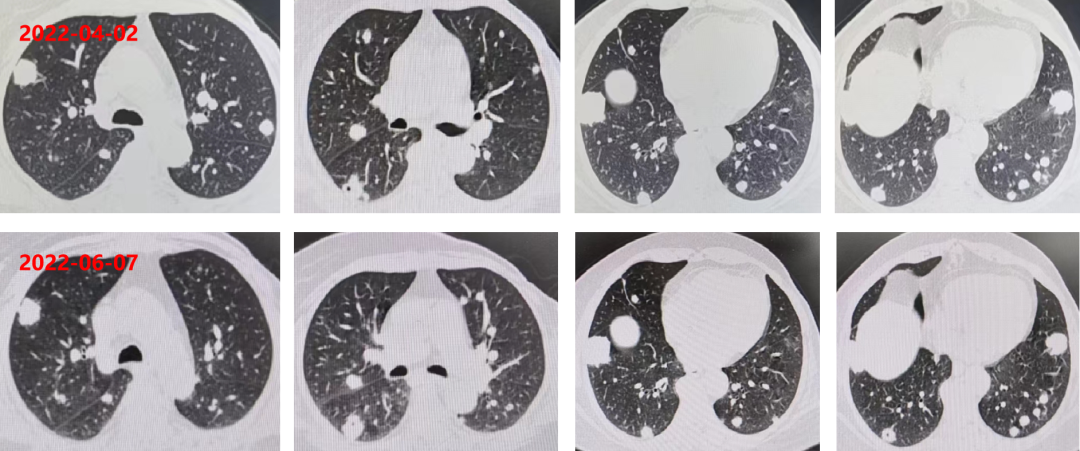

三线治疗:2022-01-14至2022-04-02 瑞戈非尼 2周期+纳武利尤单抗 4周期。

2022-04-02 复查CEA:260.6ng/ml(逐渐升高)。

胸腹部增强CT:双肺多发转移瘤,较前片相比增大(较大者位于右肺下叶,长径约3.4cm,靶病灶增大,出现新病灶),直肠壁和肝左叶病灶未见变化。

疗效评估PD。

四线治疗:曲氟尿苷替匹嘧啶片(TAS-102)+贝伐珠单抗 6个周期。

2022-06-07 复查 CEA:266.3ng/ml。

胸腹部增强CT:双肺多发转移瘤,较前片相比变化不大(较大者位于右肺下叶,长径约3.3cm,靶病灶与非靶病灶未见明显变化)。

疗效评估SD。

04 疗效评估

晚期结肠癌患者多线治疗后,选择贝伐珠单抗联合曲氟尿苷替匹嘧啶片(TAS-102)方案治疗,用药4周期后,患者肿瘤标志物CEA上升趋势趋缓,复查肿瘤控制稳定。目前该方案为患者带来了约3个月的生存获益,仍在治疗中。